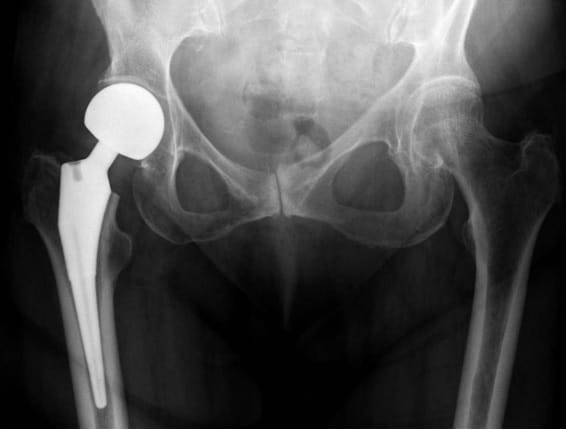

مفصل الحوض هو أحد أكبر مفاصل الجسم يشتمل على عظم طويل مع قمة مستديرة الشكل، ويشكل نقطة التقاء واتصال جذع الجسد بالساقين، وله دور كبير في دعم وزن الجسم والسماح بتحريك الجزء العلوي من الساقين وتعزيز التوازن، الأمر الذي يخلق ضغطًا كبيرًا عليه يتسبب في حالاتٍ نادرة بتآكله وتضرره لدرجة يتعين على المريض على إثرها اللجوء إلى عملية تغيير مفصل الحوض، وقد تم إعداد هذا المقال من قبل فريق عمل عيادة افضل دكتور عظام في مصر ”عيادة دكتور ياسر رضا“ خصيصًا للحديث حول هذه العملية؛ مع بيان حالات اللجوء إليها وأسباب تضرر مفصل الحوض أو الفخذ ومراحلها حتى تمام فترة الاستشفاء.

يتم خلال عملية تغيير مفصل الحوض استبدال وإزالة الجزء المتضرر من الورك أو عظم الفخذ بمفاصل وأجزاء صناعية؛ وذلك لعلاج الآلام الناتجة عن التهاب المفاصل والحالات التنكسية التي قد تصيب المفصل.

هذا الشق الجراحي سيتخلل طبقات الأنسجة، سامحًا للطبيب بإزالة الغضاريف والعظام المصابة والتالفة، مع التركيز على عدم المساس بما هو سليم منها، وبعد الانتهاء من هذه الخطوة يُزرع التجويف البديل الذي يحل محل الجزء العلوي من المفصل أعلى عظمة الفخذ، وفي النهاية يتم إدخال الجذع داخل عظام الفخذ العلوية، وتوضع فوقه الكرة البديلة التي تُحاكي حركة المفصل، ويتم في النهاية خياطة الجرح وتضميده جيدًا.